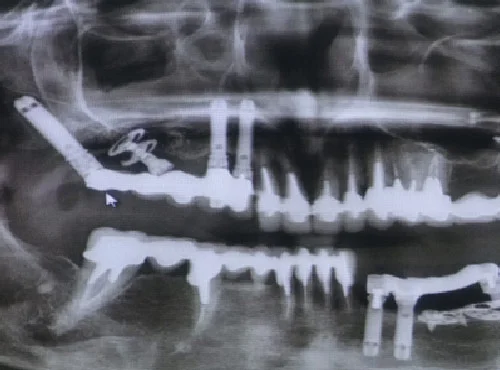

Przez 10 lat stosowaliśmy i stosujemy kilka sprawdzonych i relatywnie niedrogich systemów implantologicznych jak Osteoplant czy Neobiotech. Ostatnio do arsenału implantologii wprowadziliśmy doskonały system Straumanna oraz francuski system dedykowany szczególnie trudnym warunkom implantologicznym- system Victory. Ten system stosujemy z powodzeniem szczególnie u pacjentów 60 plus u których standardowa implantologia napotyka na olbrzymie problemy spowodowane zanikiem blaszki kostnej.

Implant dentystyczny składa się z 3 elementów: tytanowej śruby umieszczonej wewnątrz kości szczęk, tytanowego lub ceramicznego łącznika oraz korony protetycznej. Rozwiązanie, chociaż kosztowne, jest obecnie najlepszą dostępną metodą odbudowy brakującego uzębienia, gdyż zamiast maskować pustą przestrzeń umożliwia pełne estetyczne oraz funkcjonalne odtworzenie utraconych zębów.